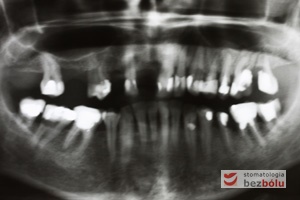

Diagnostyka radiologiczna - ortopantomogram wskazuje zęby nierokujące do usunięcia i liczne wypełnienia do wymiany

Diagnostyka radiologiczna – ortopantomogram wskazuje zęby nierokujące do usunięcia i liczne wypełnienia do wymiany